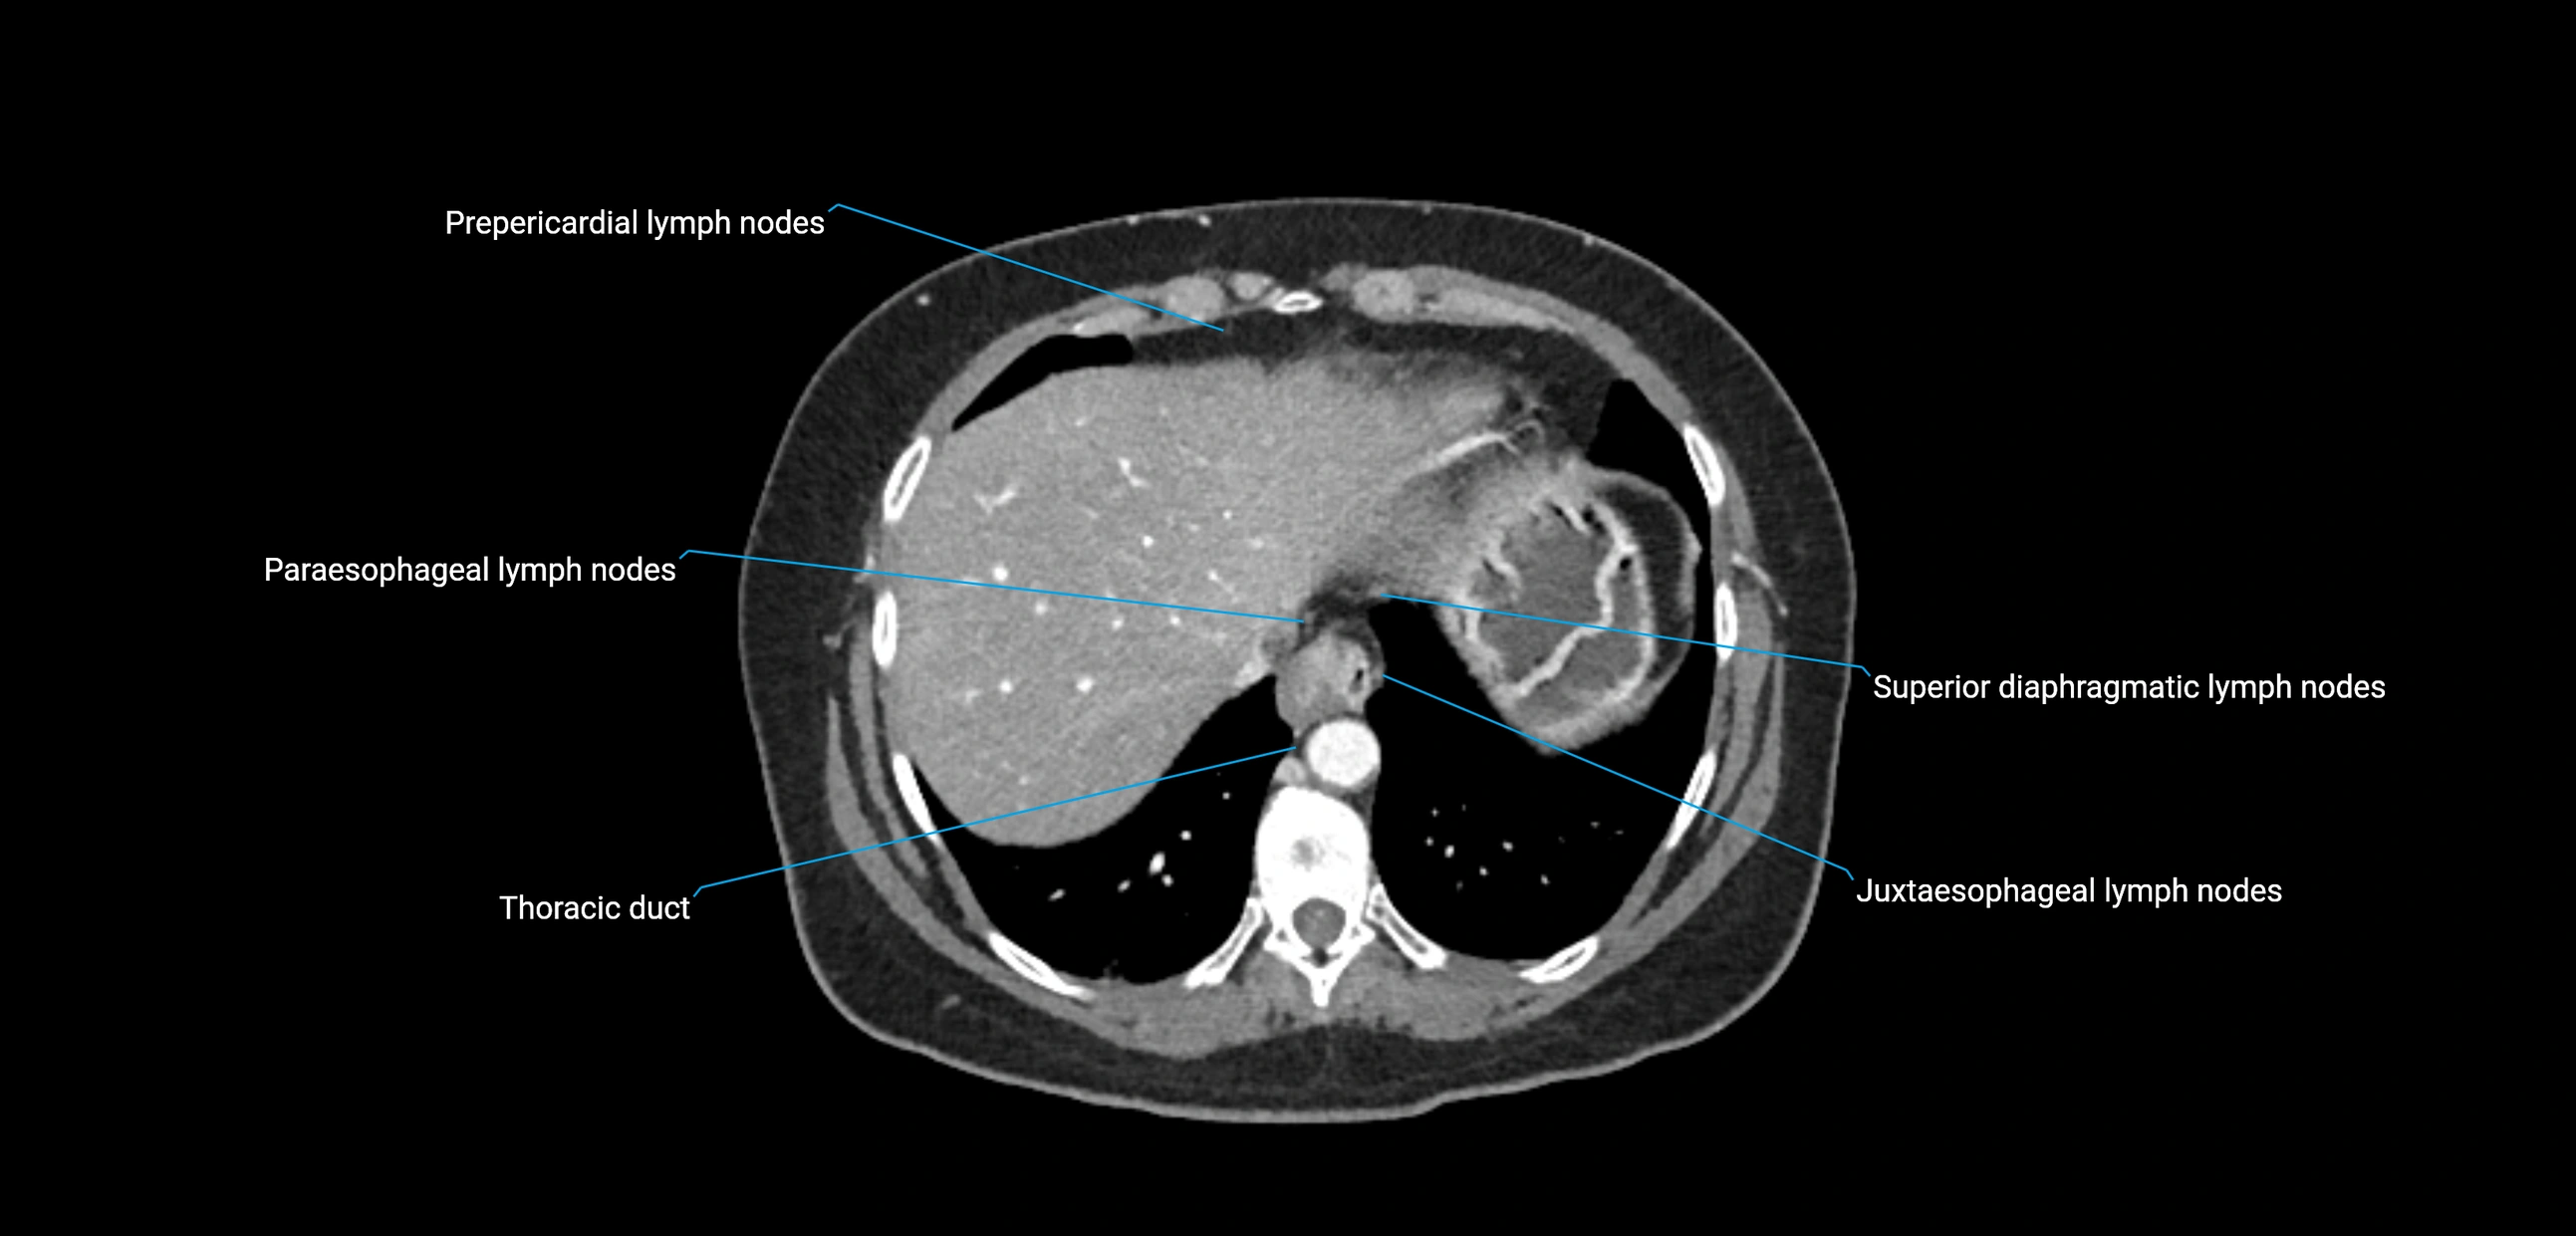

CT image

image